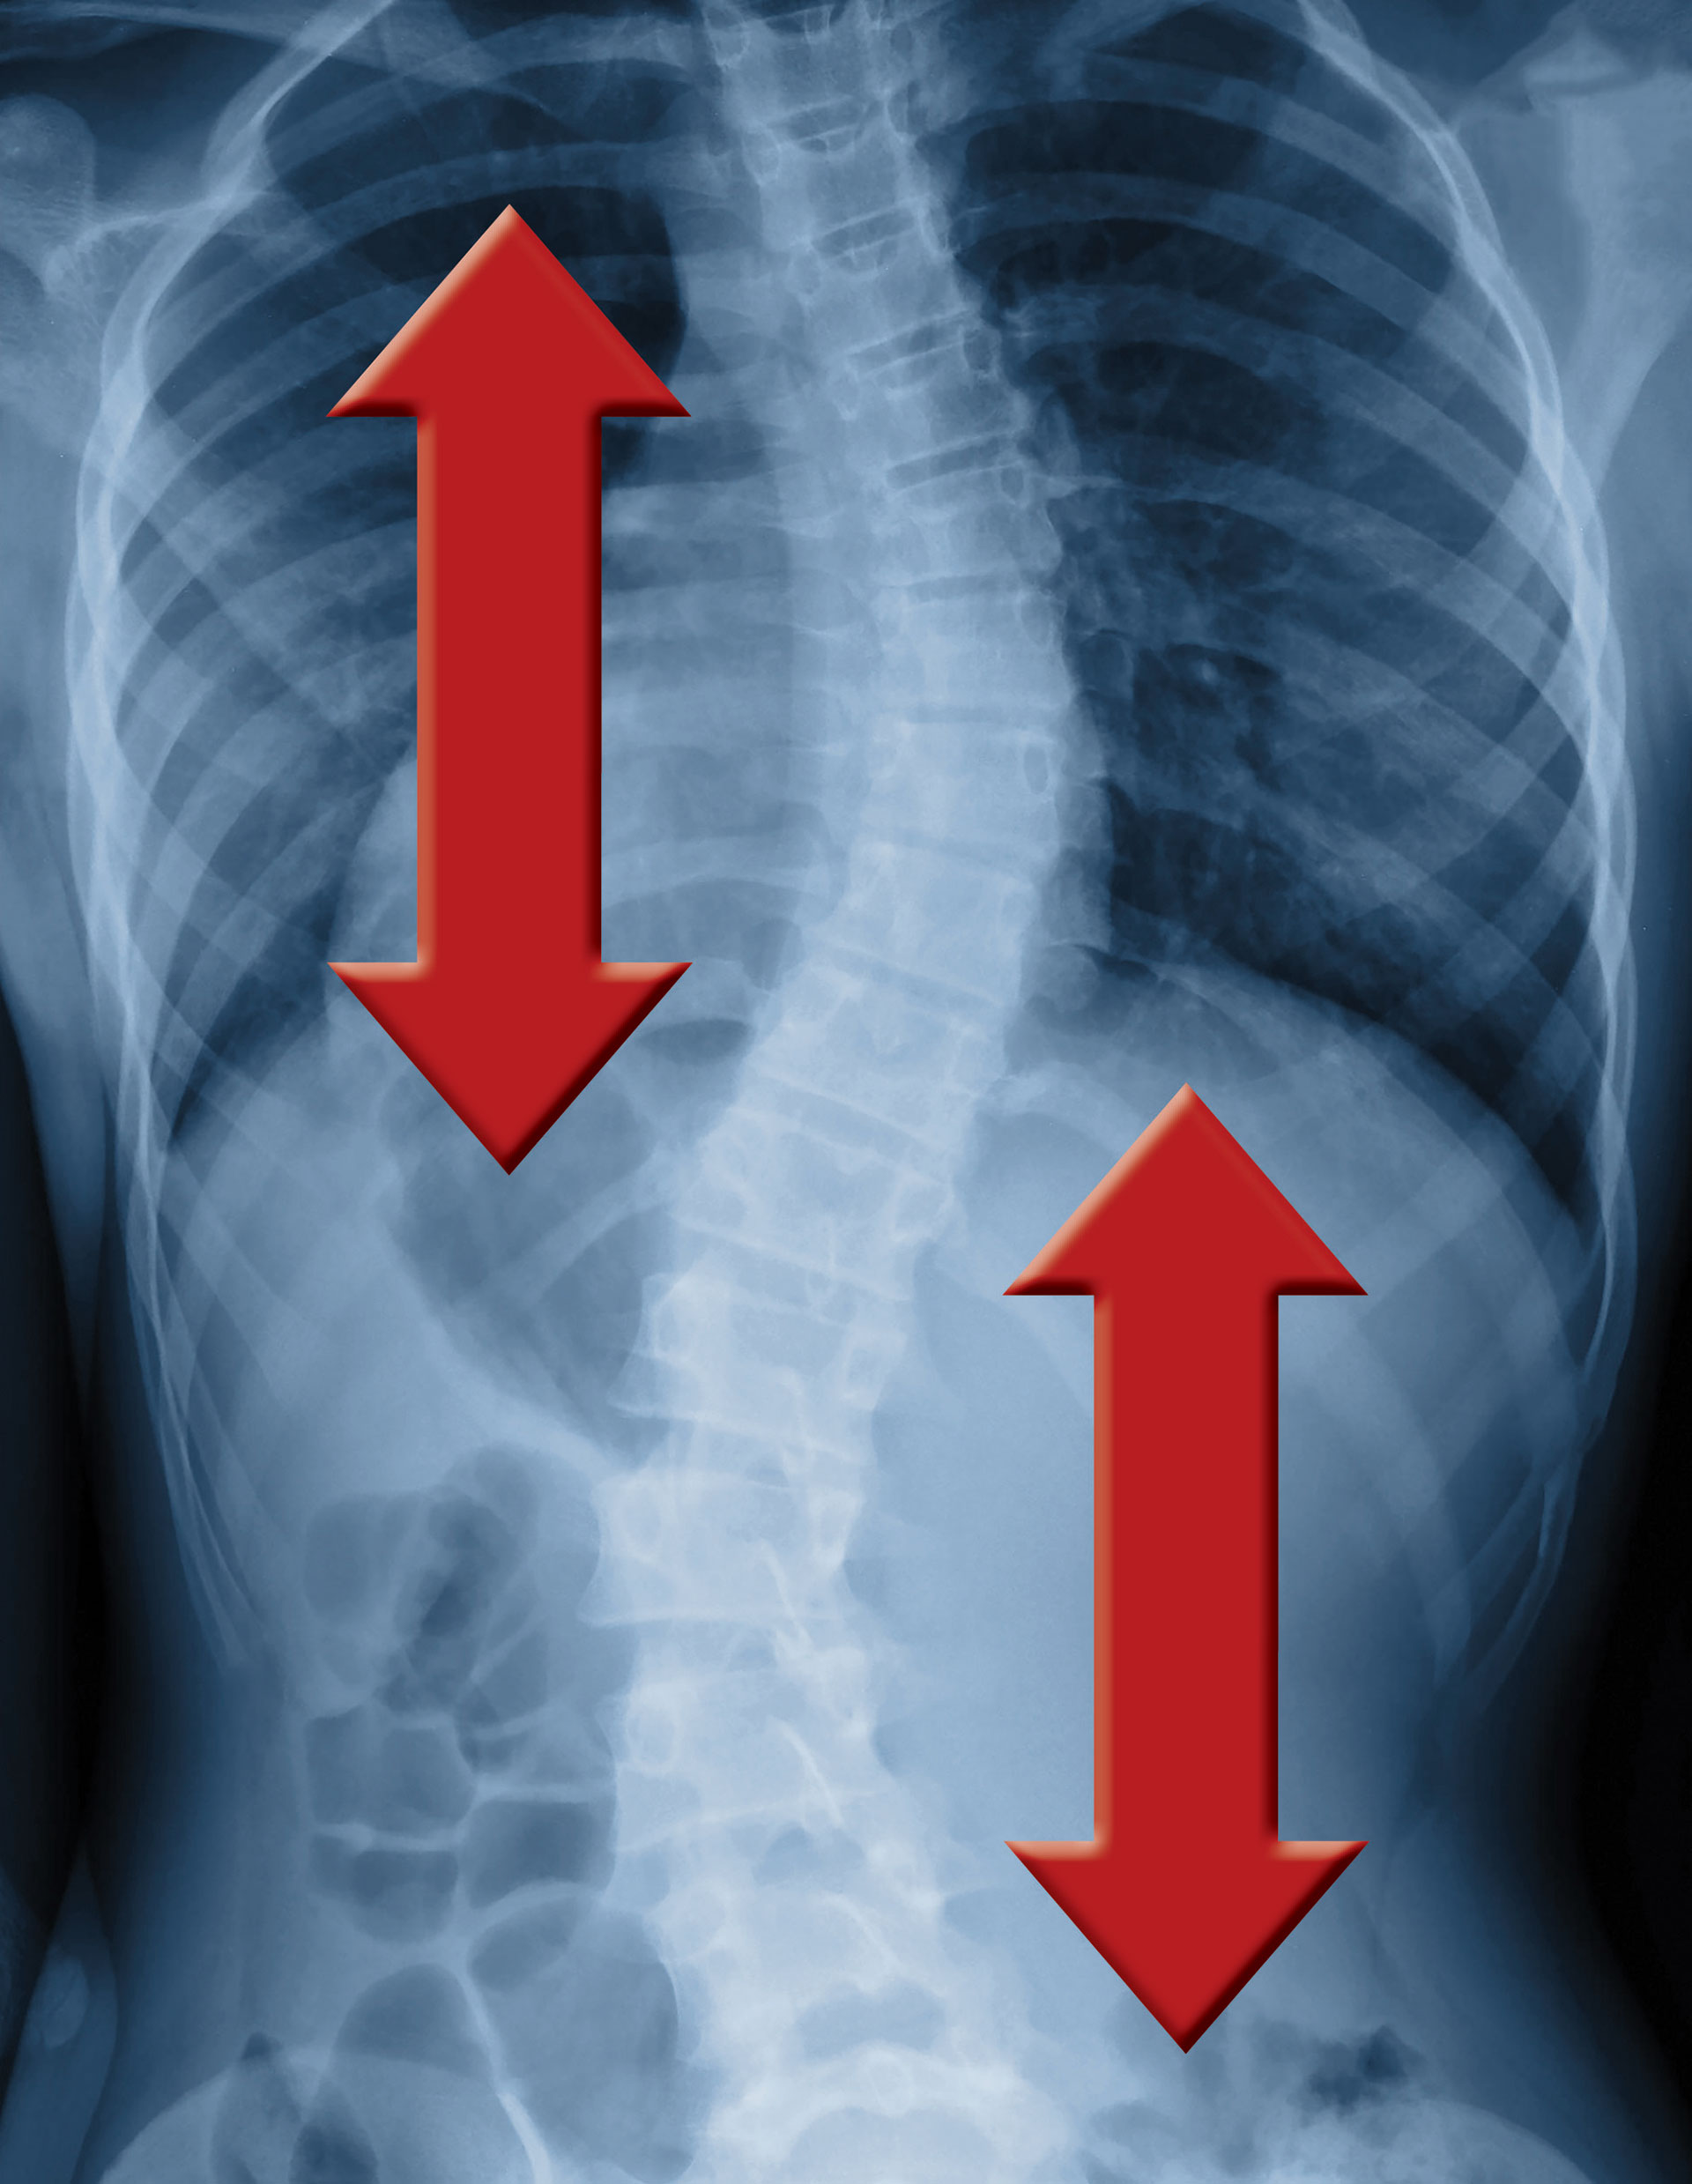

Does Inversion Table Help With Scoliosis . I have a bulging disc on my l5 s1. Inversion therapy is believed by some to aid in posture correction, which can be beneficial if you have scoliosis. Inversion tables can complement scoliosis treatments like physical therapy, bracing, and chiropractic care. I watched an athlean x video and people have sworn by what he. This method aims to relieve pressure on the spinal column and. Have used inversion tables before and they help with temporary pain relief, because they essentially create traction with gravity. Personal experiences, do they work? I am willing to try anything. Inversion therapy, which uses an inversion table, may help treat scoliosis as a form of scoliosis treatment. Explore the benefits and considerations of using inversion tables for scoliosis, including pain relief and potential to slow progression. The reduction of these spasms.